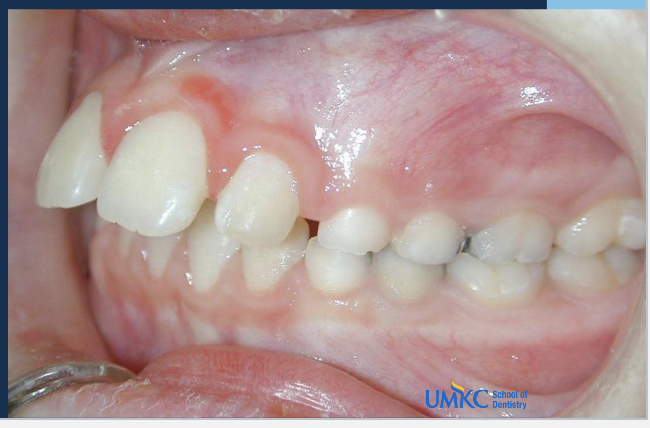

Q

A

class 2